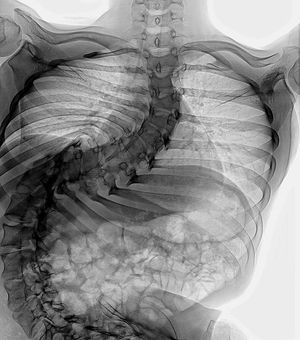

Scoliosis is a sideways curvature of the spine that occurs most often during the growth spurt just before puberty. While scoliosis can be caused by conditions such as cerebral palsy and muscular dystrophy, the cause of most scoliosis is unknown. Most cases of scoliosis are mild, but some children develop spine deformities that continue to get more severe as they grow. Severe scoliosis can be disabling. An especially severe spinal curve can reduce the amount of space within the chest, making it difficult for the lungs to function properly. Severe scoliosis is informally defined as a case of scoliosis that has progressed to the level where surgery is typically recommended (a 40-45 degree Cobb angle in adolescents, 50-55 degrees in adults). Curves of this magnitude have a very high risk of continuing to worsen. Many cases of severe scoliosis have the potential to continue to progress throughout life. Even surgery is not always successful in preventing this continued progression. In the absence of any treatment, or if treatment is started but not maintained, the Cobb angle can increase even after the spine is done growing.